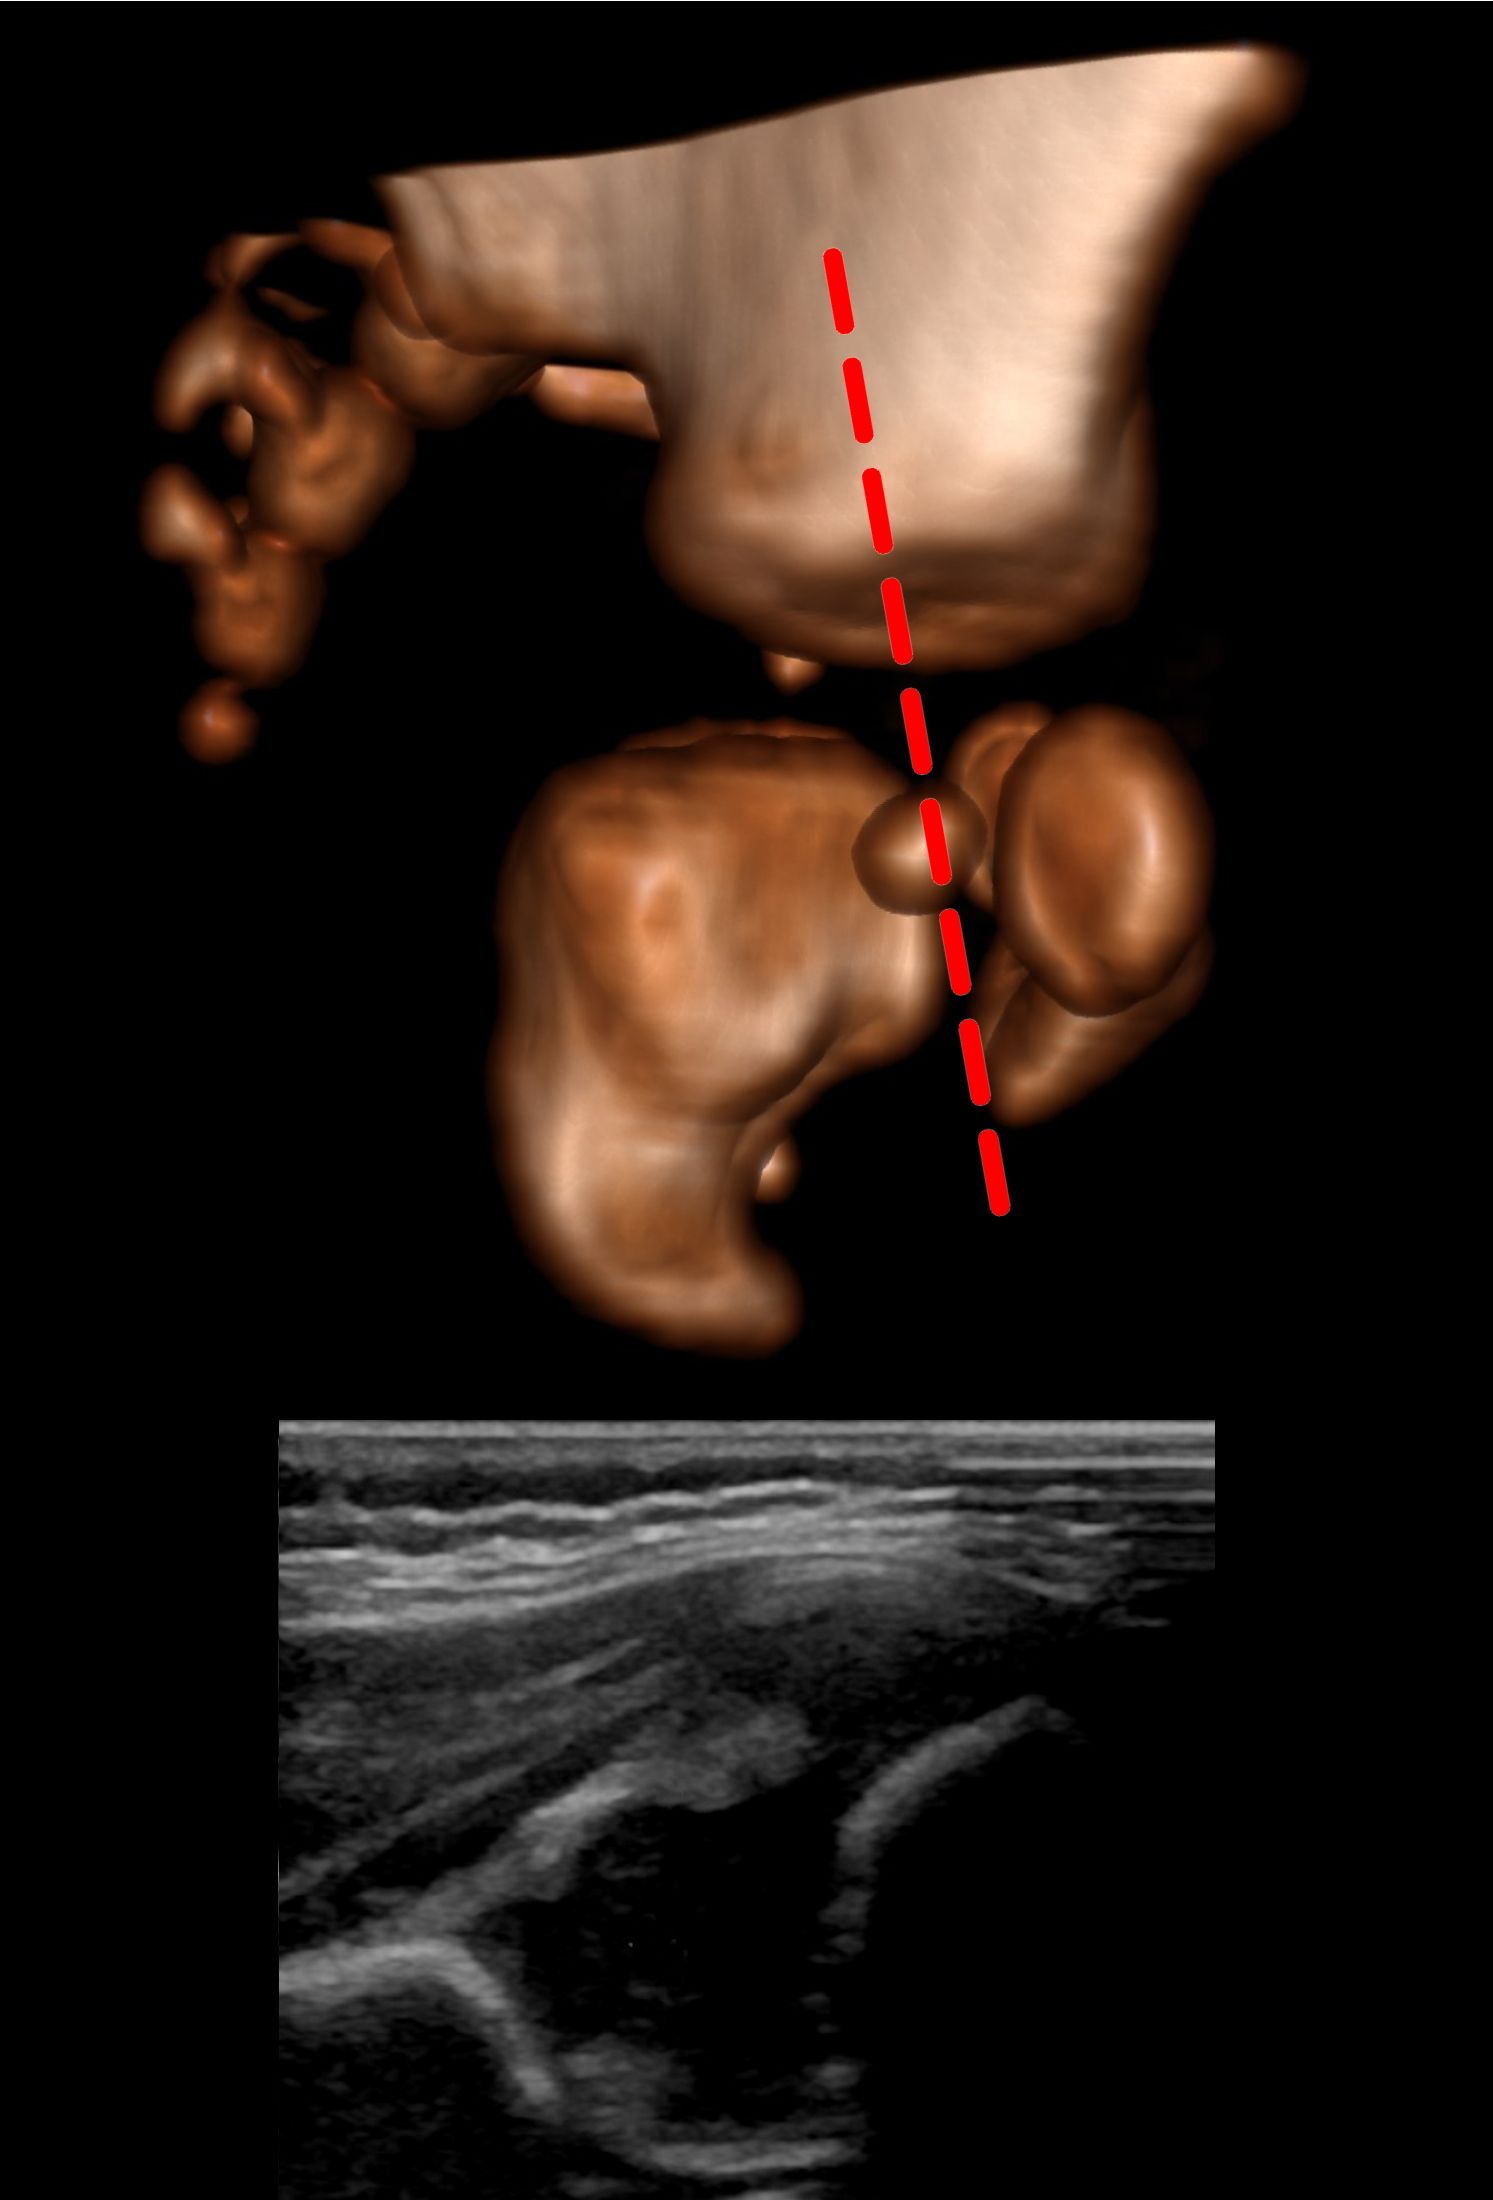

Using the Graf method the hips should be slightly flexed [1, 2]. The patient should be on their side and the probe is placed, vertically orientated, on the lateral aspect of the hip.

After identifying the osteochondral junction, the femoral head, synovial fold, joint capsule, acetabular labrum, acetabular cartilage, bony roof of the acetabulum and turning point (see earlier) should be identified. The lower limb of the ilium and the triradiate cartilage indicate the acetabular center. The ilium should then be made straight on the screen. Since, at this point, the ilium raises anteriorly and superiorly and falls posteriorly and inferiorly, to get a straight image of the ilium, you need to align the probe between the rise and the fall.

If you are scanning the right hip, rotating the probe clockwise will result in the part of the image formed by the top of the probe to raise in a curve:

And if you rotate anticlockwise, it will cause it to fall as a curve:

So to make a straight line you either chase it down by rotating anticlockwise or raise it up by rotating clockwise whilst maintaining the centre of rotation such that the structures of interest remain on screen. The opposite rotation is needed when scanning the left hip.